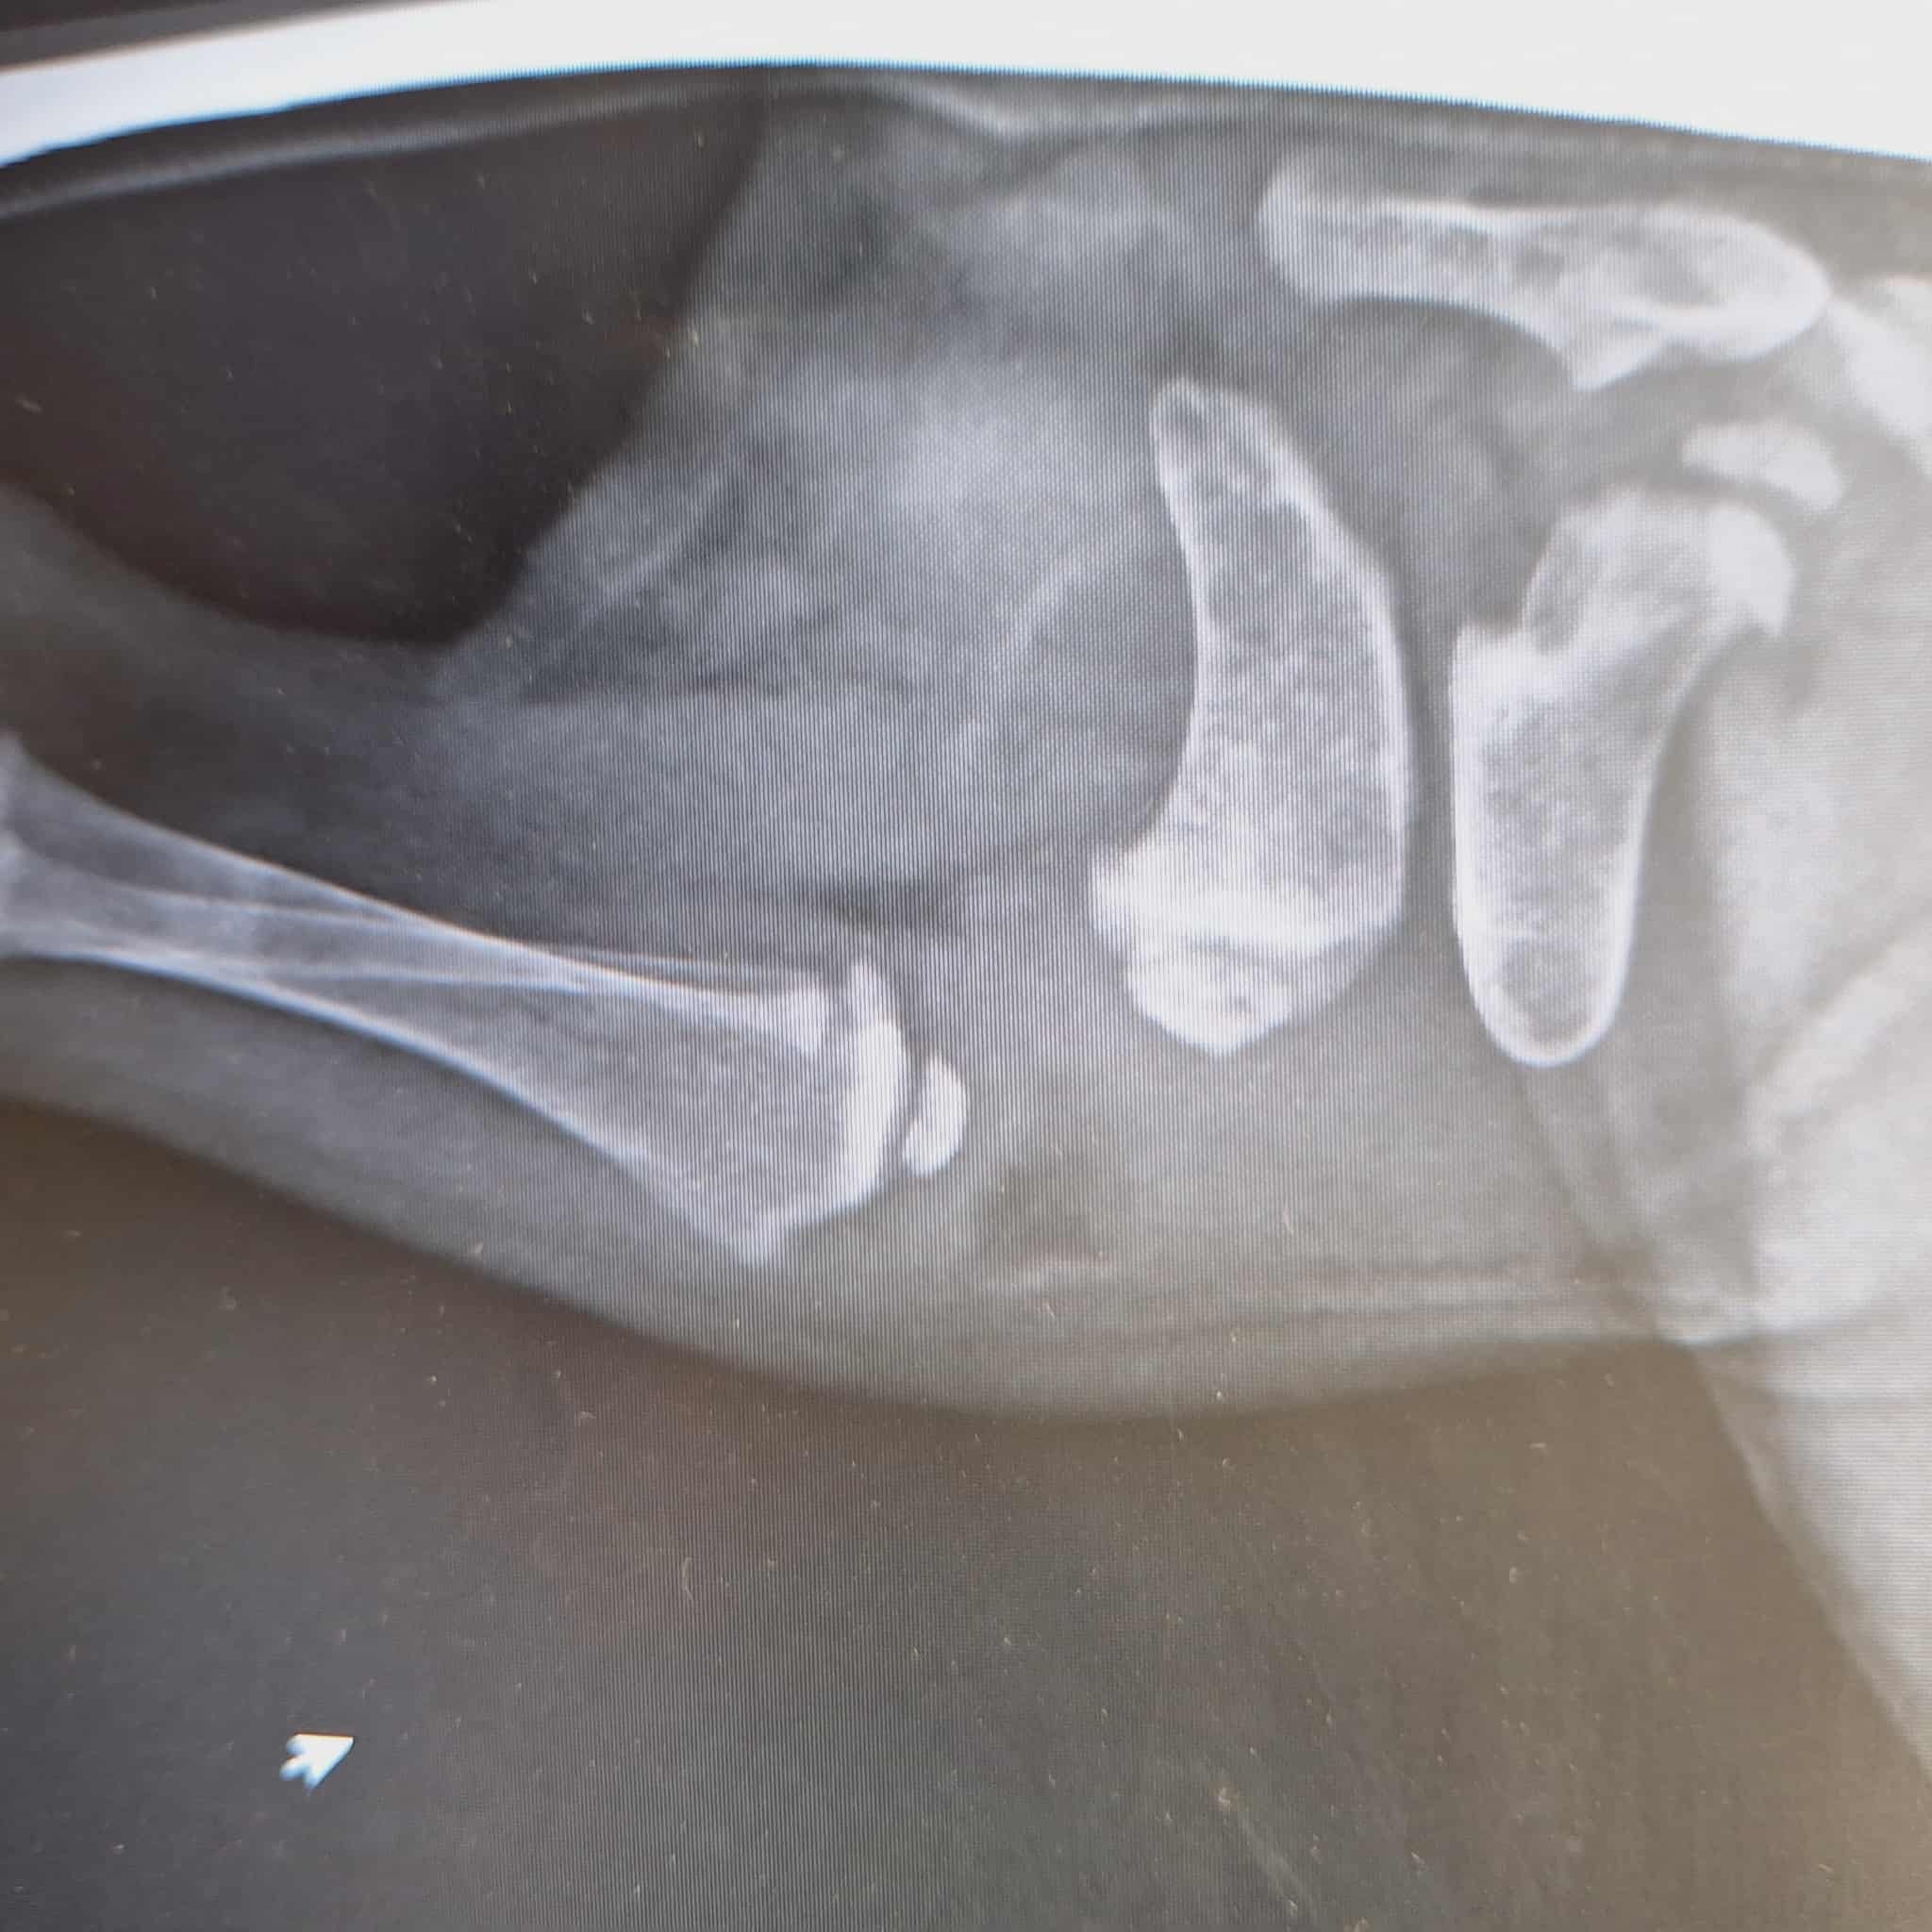

At 5 weeks she was diagnosed as being sight impaired, the extent we still not confirmed, but it doesnt look good as to her ant level of sight. But Precious's problems do not stop there, she has sustained either in the womb or after birth a broken femor bone in her hind leg. My first thougth was to pur her down as I could not see how she would be able to have a quality life and I am so devestated that my tiny pup i fought so hard for will be lost forever.

She is strong, playful, cuddly and smart, even at 5 weeks she is coping so well with her disadvantages. She has no pain in the broken leg, it has actually mending in this awkward postition, the vets have confirmed there is no rush to do anything serioius at this stage. My plan is to talk to the surgeon next week and plan a timeline and future for Precious, but I am unable to afford a repair surgery at this stage. So i am reaching out for some help from my friends to help me save her and give her a joyful life as a blind dog with either 3 legs or one rebuilt leg. I am unsure of what her treatment will look like at this stage but i will always be greatful for the communities help and support through this tough time. kind regards Kerry

Update: Precious is now in surgery to repair and pin her broken leg, I will update hew progress tonight :) Its very stressful waiting for news